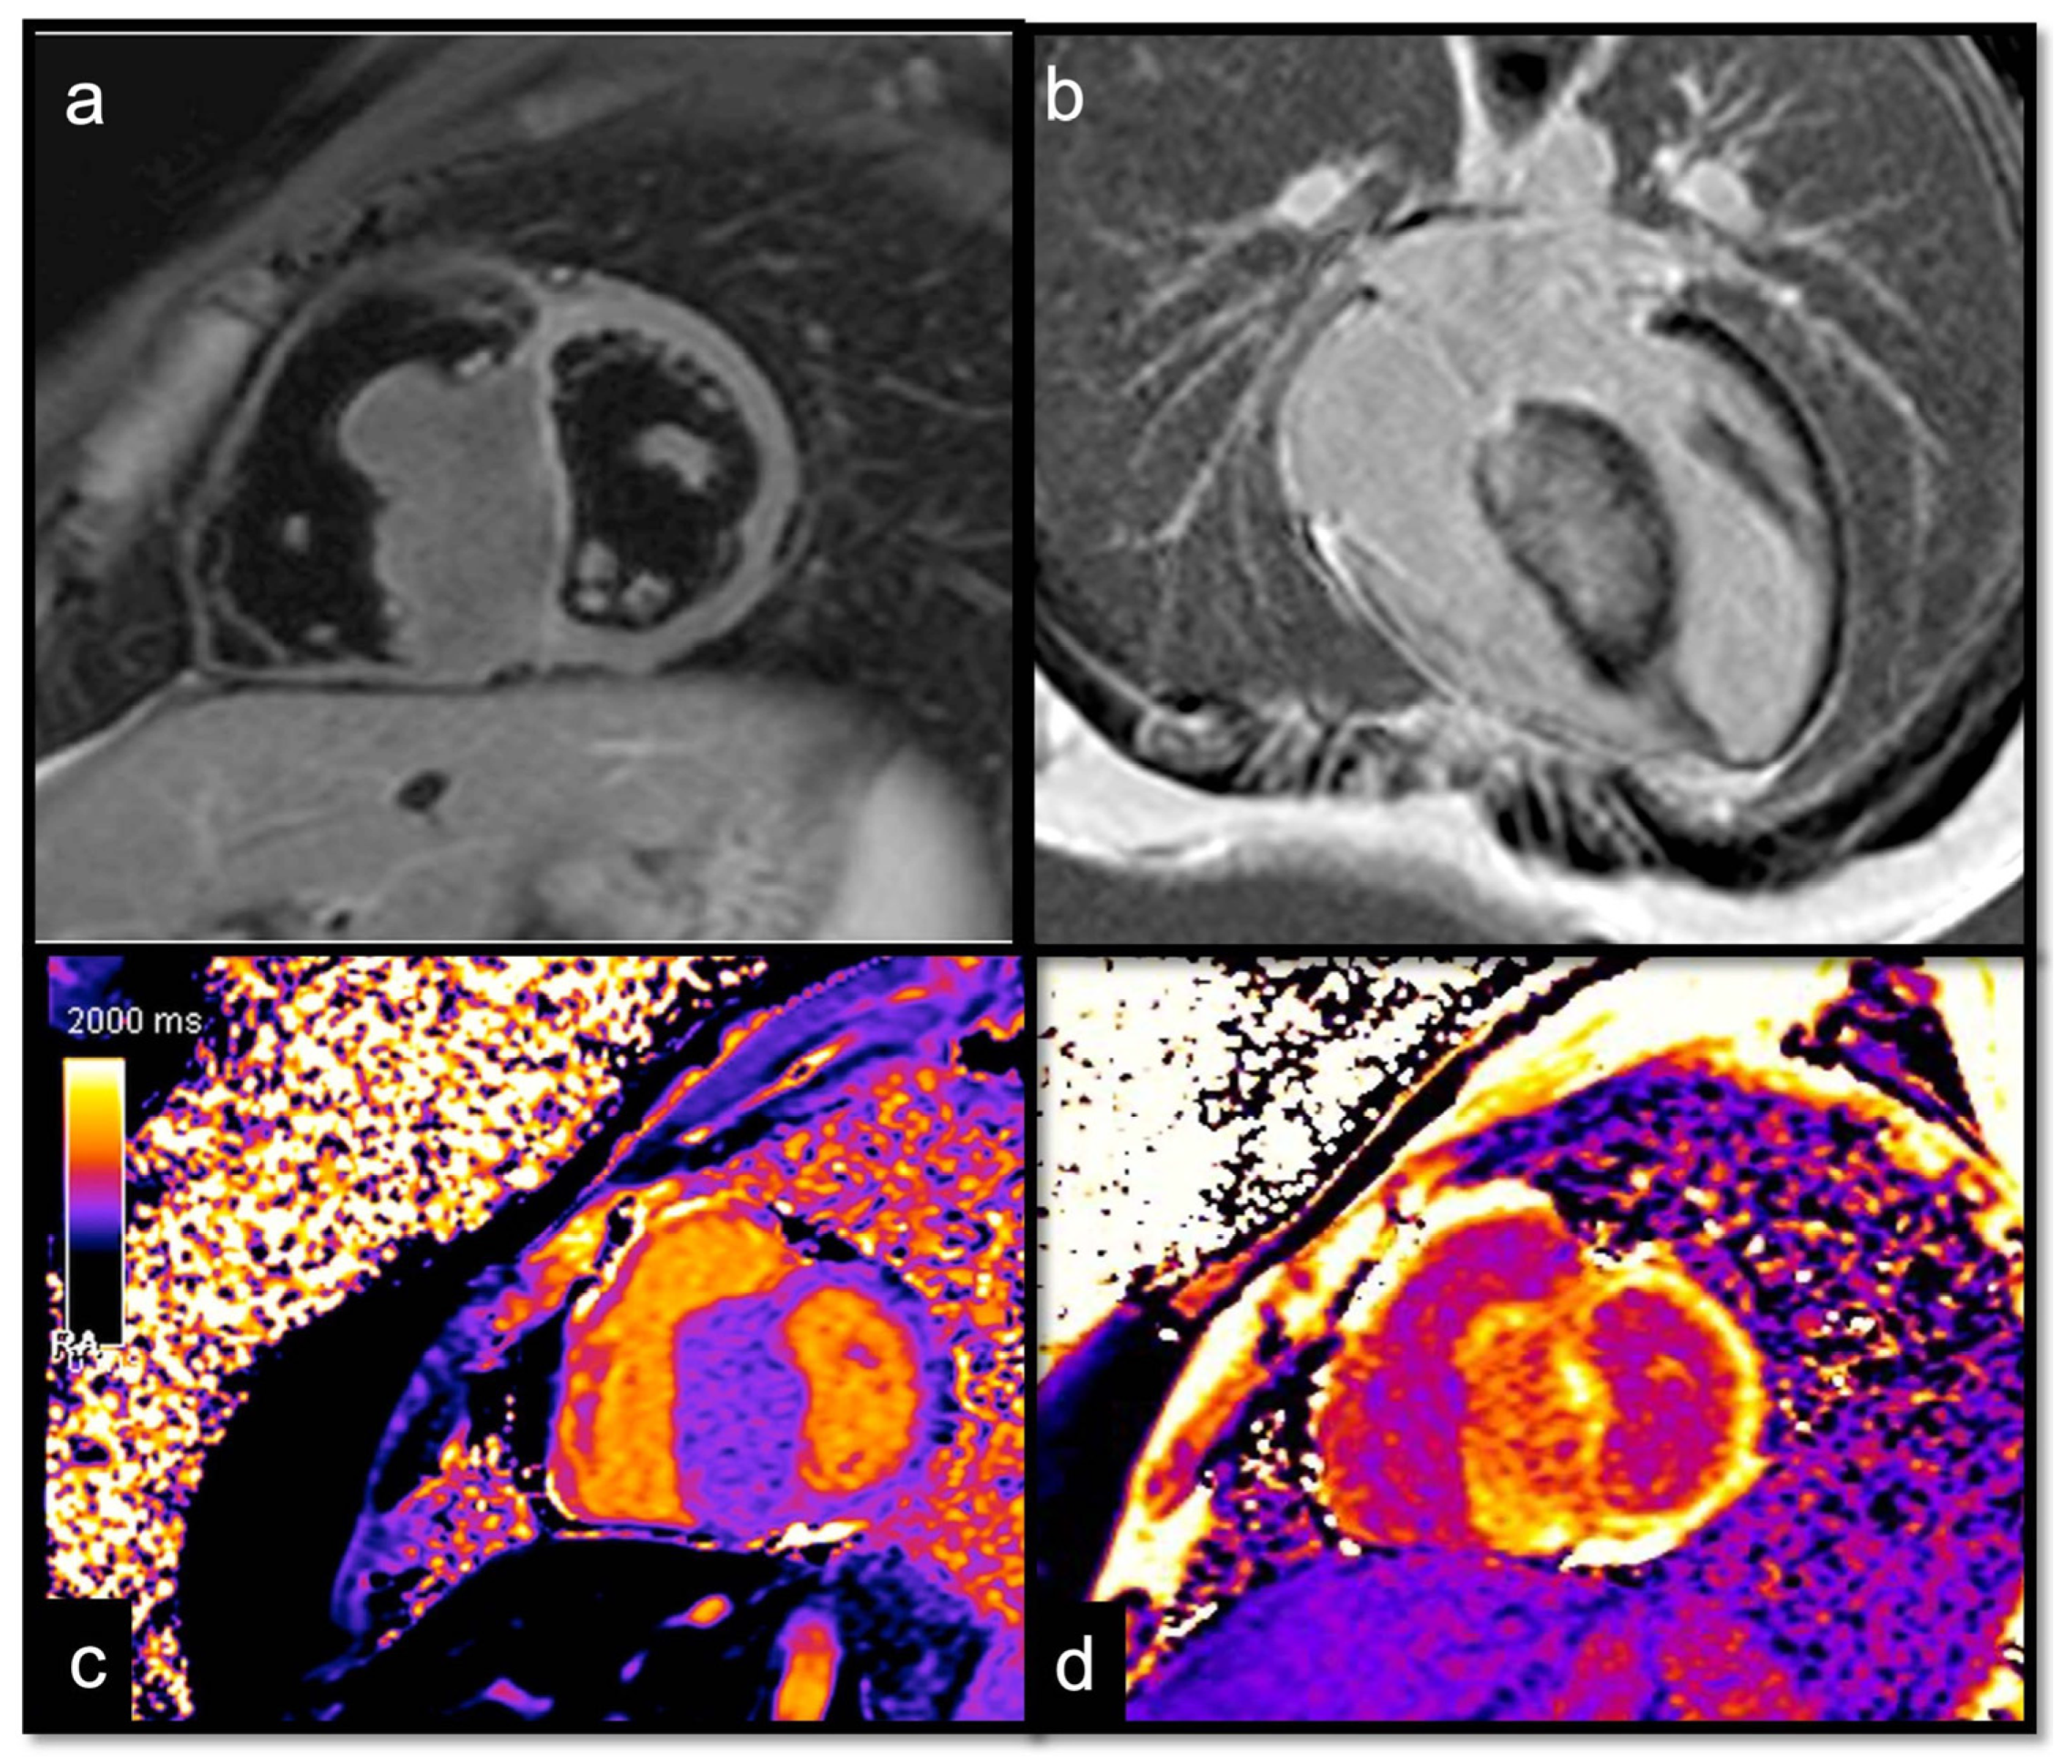

7.2.6. T1 and T2 Mapping

Utility:

Parametric mapping is very useful in patients undergoing evaluation for suspected myocardial disease, and it is also beneficial for the evaluation of cardiac masses. Recent studies evaluating T1 and T2 mapping suggest that parametric mapping increases the ability of CMR to differentiate between cardiac thrombi and masses [58,60,61,62,63]. The analysis of intracardiac tumors and masses with T1 and T2 mapping revealed important differences among the different subtypes, generating multiple T1/T2 profiles according to the etiology [46]:

- Long T1/long T2 for most tumors, whether benign or malignant, with different degrees in particular for the T1 (close to the myocardium for rhabdomyoma, long or very long for myxomas [65] and fibroelastomas)

- T1 mapping allows for highlighting the difference between recent (<1 week) and old thrombi (>1 month), as recent thrombi have a significantly shorter T1.

Caspar et al. did not observe any differences concerning T2 mapping sequences in their cohort, and T2 is long compared with the myocardium, regardless of the age or location of the thrombus. This might be explained because it is very uncommon to diagnose a thrombus in a very acute phase when T2 is still long.

Red Flag (!): Heterogenous maps due to hemorrhage or necrosis inside the mass suggest malignancy.